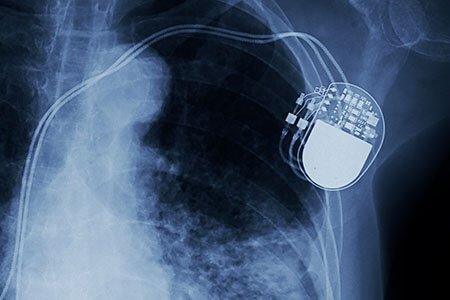

Pacemakers: A pacemaker is an electronic device, to assist the heartbeat in a specific way. It has few insulated wires, battery and a circuit, programmed to regulate the electrical impulses in the heart. It is surgically placed by a cardiologist below the collarbone in the chest. Pacemakers may be implanted temporarily or permanently and may or may not be monitored by the doctor from the hospital.